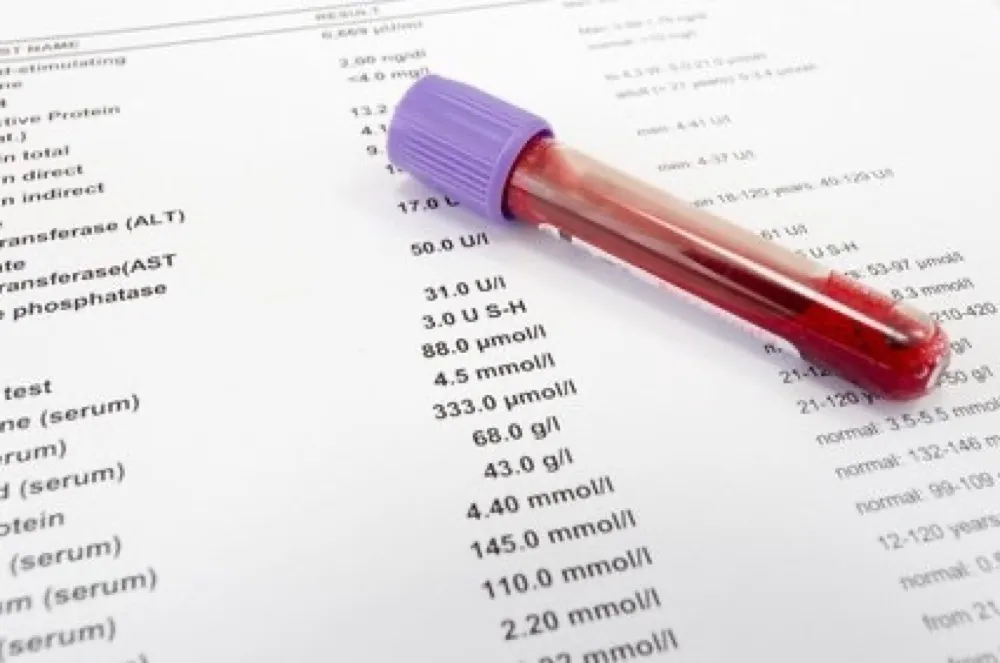

Ondansetrona e o risco de morte súbita em hemodiálise

Ondansetrona e o risco de morte súbita em hemodiálise

Como assim risco de morte súbita com Ondansetrona? Atenção especial aos pacientes com polifarmácia e risco de QT longo!

Novidades KDIGO 2024: Diagnóstico

Novidades KDIGO 2024: Diagnóstico